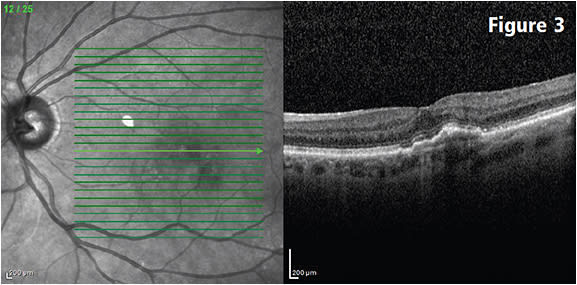

In addition, treat-and-extend strategies can lessen the burden on practices as well as patients (Figures 1-3).

Figure 3: Eighteen months after the baseline exam, following nine bevacizumab injections using a treat-and-extend strategy. The prior three injections were administered at three-month intervals. Shows no significant change from the study performed at the three-month point, still without any macular fluid. Visual acuity improved to 20/20. COURTESY CHRISTOPHER HAUPERT, MD